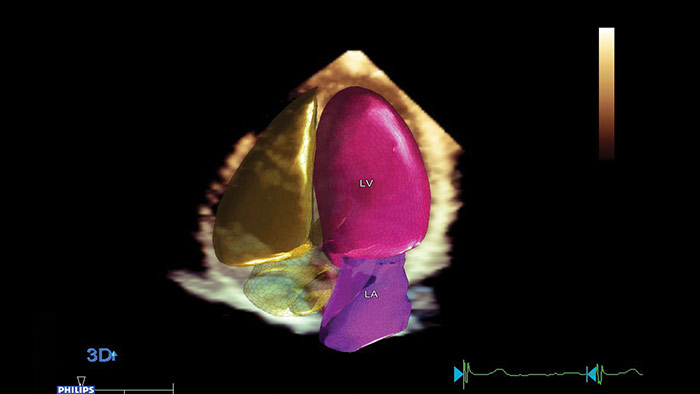

Anatomical Intelligence for Ultrasound (AIUS) di Philips, una tecnologia progettata per potenziare il sistema ecografico. Funzionalità avanzate di modellazione degli organi, sezionamento delle immagini e quantificazione convalidata per agevolare l'esecuzione degli esami e favorirne la riproducibilità, che offrono nel contempo nuovi livelli di informazioni cliniche per rispondere alle sfide economiche e cliniche poste dagli ambienti sanitari odierni.

Le funzionalità AIUS spaziano dall'automazione di passaggi ripetitivi fino all'analisi computerizzata completa di dati non elaborati, con una minima interazione da parte dell'operatore. AIUS è in grado di fornire una documentazione di screening avanzata e misurazioni assistite, oltre al rilevamento di organi e strutture per la registrazione automatica e la quantificazione avanzata.